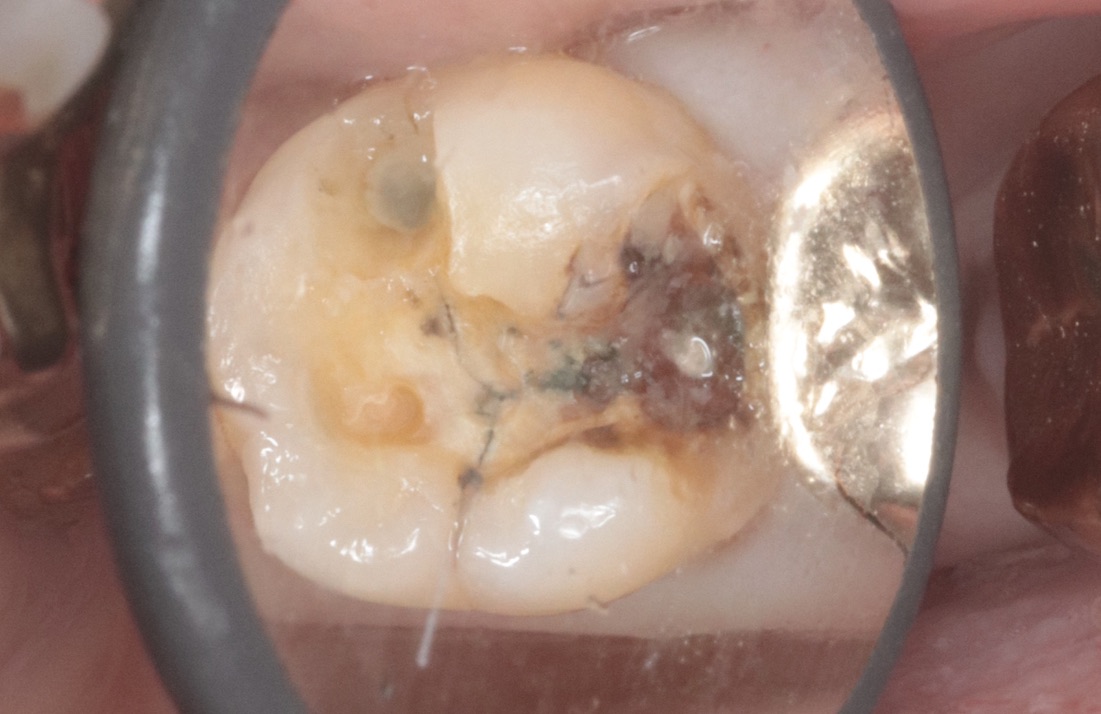

奥歯の金属が外れたということで来院されました。

写真のように、中が黒くなっており、虫歯の状態でした。

今回はセラミックにて修復を行うことにしました。

残っているエナメル質が薄いところがあったので、インレータイプではなくアンレータイプで修復を行います。